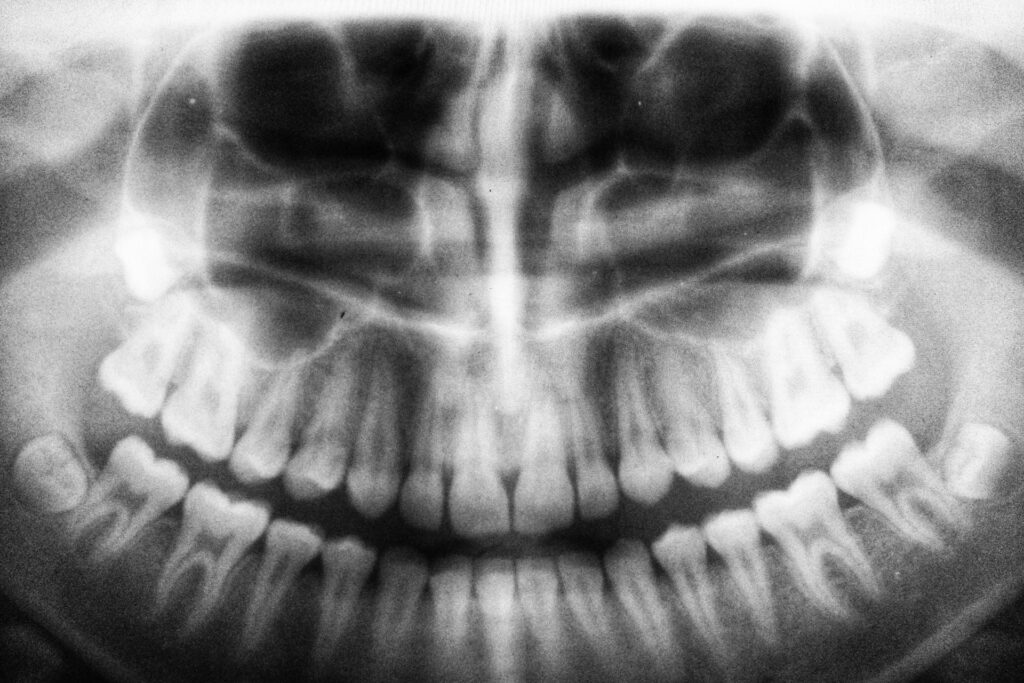

Forscher haben über 8.000 ältere Menschen begleitet und herausgefunden, dass schneller Zahnverlust auf Entzündungen und Mangelernährung hinweisen kann. © Unsplash